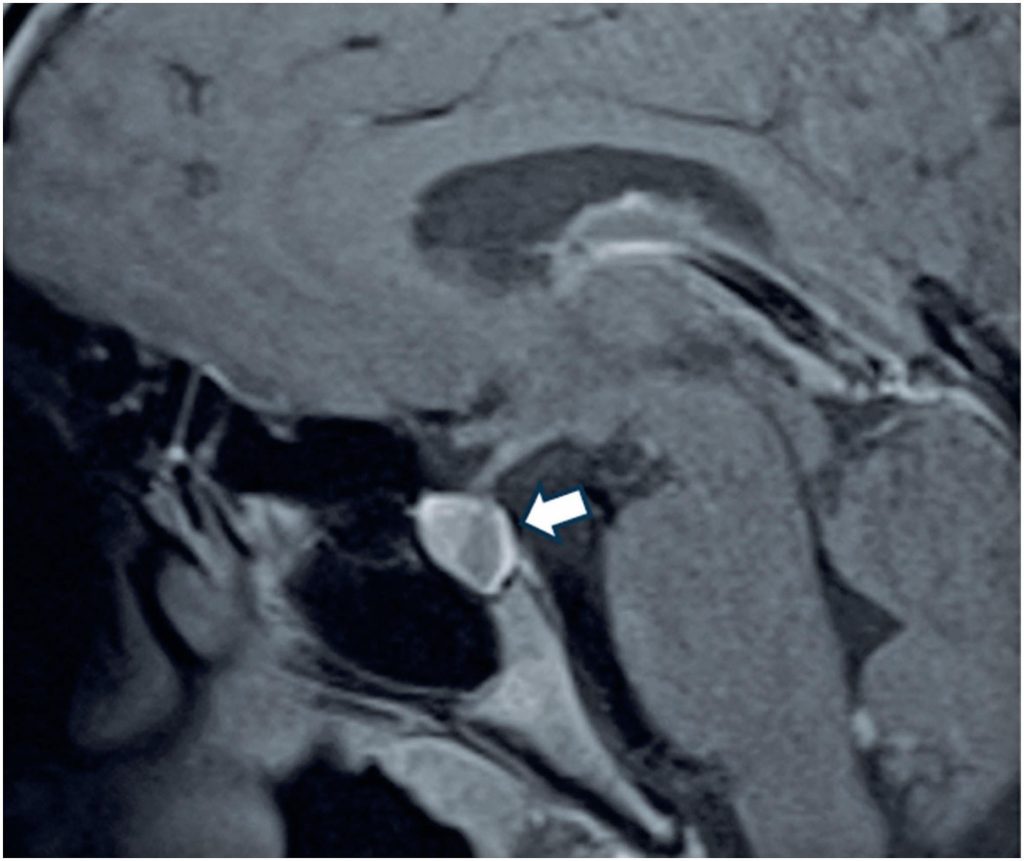

The 48,XXYY syndrome is a rare sex chromosome aneuploidy associated with diverse physical, developmental, and endocrine abnormalities. This case report highlights a 15-year-old male with 48,XXYY syndrome presenting with hypopituitarism and a Rathke’s cleft cyst, offering insights into the interplay between genetic syndromes and pituitary dysfunction. The patient exhibited hyperprolactinemia, central hypothyroidism, central hypoadrenalism, and elevated gonadotropin levels. Brain magnetic resonance imaging revealed a cystic lesion within the sella turcica, consistent with a Rathke’s cleft cyst. The patient also had autism and severe essential tremor. Physical examination revealed a reduced testicular volume without gynecomastia, and genetic analysis confirmed a 48,XXYY karyotype. Hormone replacement therapy with prednisone and levothyroxine was initiated, resulting in adequate hormonal replacement. Follow-up magnetic resonance imaging demonstrated stability of the pituitary cyst, with no evidence of progression. This case highlights the importance of hormonal evaluation in patients with rare sex chromosome aneuploidies. Routine pituitary hormone evaluation and imaging should be integral to the care of individuals with 48,XXYY syndrome. These findings highlight the value of a multidisciplinary approach that integrates endocrinology, genetics, and neurology to address the complex needs of these patients. The association between 48,XXYY syndrome and Rathke’s cleft cyst raises intriguing questions about the potential links between sex chromosome aneuploidies and pituitary abnormalities. This report emphasizes the need for comprehensive endocrine and structural assessments to optimize patient outcomes by contributing to the limited literature on 48,XXYY syndrome.